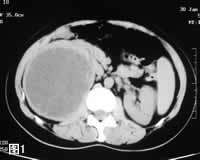

CT:平扫示右肾上极低密度类圆形占位,CT值30~35HU,边缘光滑(图1)。增强扫描可见肿瘤呈多房状,间隔强化明显,外缘及腔内未见强化(图2)。